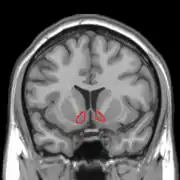

| Прилегающее ядро на МРТ головного мозга человека |

Сенсибилизация — концепция в психологии, объясняющая тот феномен, что люди после повторного приема вызывающего болезненное пристрастие вещества, независимо от вызываемого им чувства удовольствия и часто вопреки пониманию вреда, испытывают ещё большее пристрастие и тягу к повторному потреблению[1][2]. Концепция была предложена на основании опытов, в ходе которых экспериментальным животным вводили психостимуляторы, причём повторное введение лекарства вызывало усиленную психомоторную реакцию на введение прежней дозы[3][4]. Считается, что причина этого явления может быть связана со стойкими изменениями в прилежащем ядре, компоненте так называемого центра удовольствия.

Сенсибилизация — в разной степени выраженный у разных индивидов, специфический в отношении определенного вещества эффект, не связанный с перекрёстными реакциями, хотя она также может быть эффектом многих индуцирующих зависимость лекарств. Этот процесс является противоположностью формированию привыканию (габитуации). Сенсибилизация приводит к снижению чувствительности в области прилежащего ядра. Вследствие этого, ядро может активироваться уже минимальными дозами, а иногда и ассоциированными с наркотиком раздражителями. Так возникает «управляемая влечением» мотивация с импульсивным побуждением к действию. Эта мотивация манифестирует, прежде всего, в таких подкорковых центрах как полосатое тело. Эта так называемая «возбуждающая сенсибилизация» может объяснить феномен, заключающийся в том, что зависимый от какого-либо вещества больной, независимо от субъективного чувства удовольствия, испытывает чувство, вынуждающее снова найти и принять соответствующее наркотическое вещество. При этом данный процесс и следующие за ним действия и поступки в их целенаправленности не воспринимаются больным как насильственные, так как в этом случае не обязательно дело доходит до осознанной непреодолимой потребности в соответствующей субстанции.